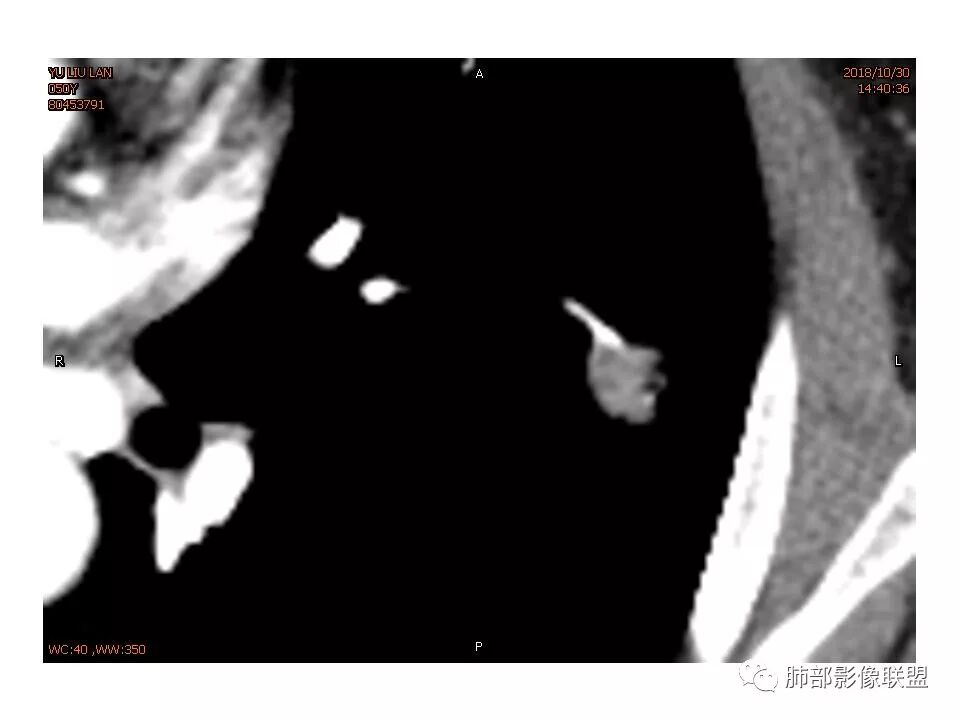

女,50。实性不规则结节,大小12*13mm,分叶、毛刺、胸膜凹陷,牵拉力强,增强渐进性强化,动脉期强化20,静脉期还有进一步强化。边缘强化,点状坏死。

其内血管被破坏。

血管贴边,但没有明显压迫征象。明显强化。局部膨隆,毛刺,分叶。

胸膜牵拉,这些都支持恶性

请问南边老师,这个进入结节的血管算增粗吗?

南边:

稍增粗

1.胸膜下略不规则实性密度结节影,孤立,缺乏典型深分叶,可见淡薄边界模糊磨玻璃晕,可见相对细长软毛刺。

2.如南边老师分析,病灶缺乏边缘膨隆优势,甚至部分平直内收。

3.病灶收缩力不强,整体强化程度不显著。

4.综上,病灶更符合炎性,如隐球菌感染等,而不大符合肺腺癌。具体到机化性肺炎略有些出乎预料。